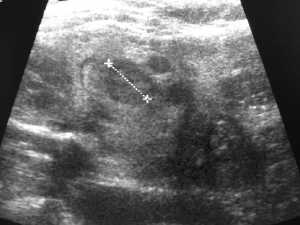

Als Ultraschallluntersuchungen werden in meiner Ordination die ergänzende Mammasonographie,also die Ultraschalluntersuchung der Brust durchgeführt.Des weiteren biete ich Utraschalluntersuchungen der Oberbauchorgane, der Nieren, sowie der Unterbauchorgane an, außerdem noch alle Weichteile, wie Schilddrüse, Sehnen und Gelenke.

Vorbilder Ultraschalluntersuchung: